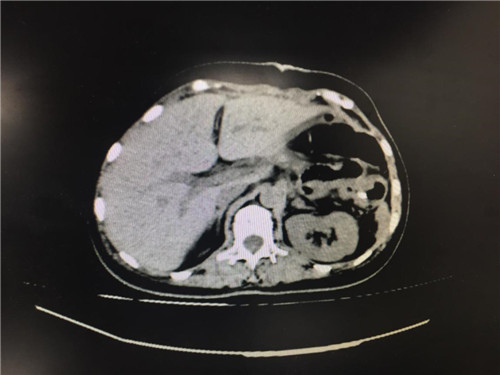

2月12日,普外科收治了一名女性患者,该患者入院一个月前,无明显诱因出现上腹部疼痛不适,呈间断性,向腰背部放射,有恶心,无呕吐,近一个月体重下降了5kg。门诊查上腹部CT提示:胰颈部新生物并胰管扩张;副脾。

患者病情复杂,在潘承恩教授和全科医生的讨论下,结合检验及检查结果,术前胰腺颈体部肿瘤诊断明确,科室积极制定手术方案,详细向家属探明病情并取得合作。2月21日,由普外科史和平主任、梁鹏锋医师主刀,在王谦、李垚磊医师配合下,成功对该患者实施了剖腹探查、全胰腺切除、脾脏切除术。手术中发现,患者胰腺颈体部可触及一大小约4cm包块,胰头部质软,胰腺体尾部质硬,遂决定行胰腺颈体尾部切除及脾脏切除术。在胰腺近侧断端切取部分胰腺组织送术中快速冰冻,提示查见异型增生的胰腺腺泡样组织,联系病理科考虑癌细胞残留,术中向家属谈明病情并取得同意,遂行胰十二指肠切除术,手术顺利,术后生命体征平稳,并于术后第四日进行了复查CT结果良好。